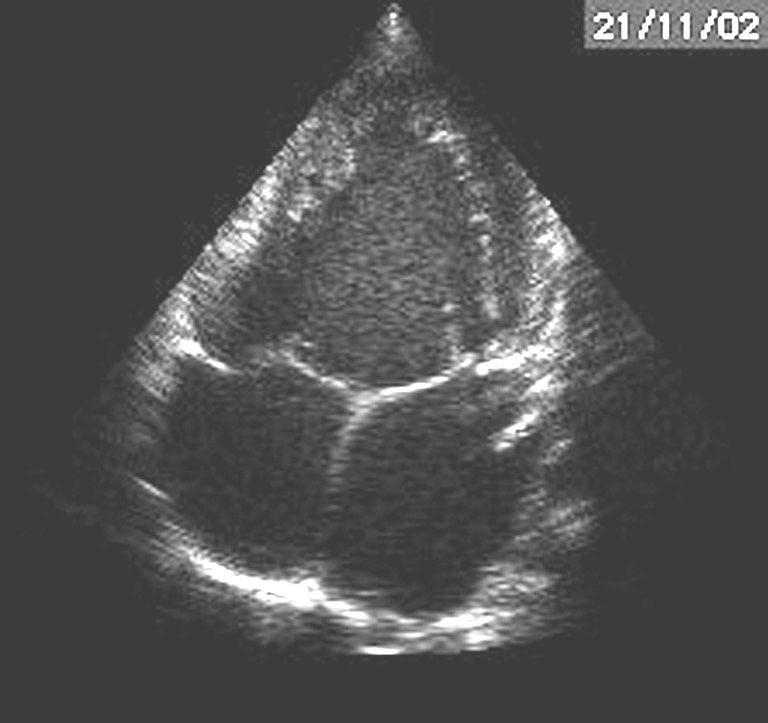

- Shunts gauche – droite dominant la scène.

- Communication interventriculaire (CIV) large.

- Persistance du canal artériel.

- Canal atrioventriculaire (chez le trisomique 21).

- Risque d’hypertension artérielle pulmonaire (HTAP) irréversible si le shunt est opéré trop tard. Chirurgie en général dans la première année de vie (figures 3 et 4).